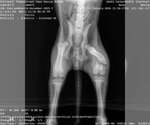

Dog Breed: German Shepherd Dog / Doberman Pinscher (medium coat). Adoption Fee: 400. Roxy is a goofy, silly girl with a huge heart and an even bigger love for life. All she really wants is someone to love her and a buddy to play with—she’s happiest when she’s being her playful, joyful self. Her story hasn’t been an easy one. Roxy was found on the side of the road in the rain after being hit by a vehicle, suffering multiple serious injuries including a broken shoulder, tail, femur, and even a break in her back. Thanks to the incredible team at Auburn University, she received life-saving surgery and care—and today, she’s doing amazingly well. Because of what she’s been through, Roxy does have some lingering PTSD, but she continues to grow more confident every day. She’ll need a patient, understanding home that will support her as she continues to heal and thrive, especially as she gets older. Roxy absolutely loves people and is wonderful with kids, though she can be a bit jumpy when she gets excited, so a home without very small children would be best. She also loves cats… unfortunately, the feeling isn’t always mutual. She would truly shine in a home with another friendly, playful dog who can be her companion. Due to her injuries and breed, Roxy cannot be spayed until she is at least one year old to allow her body to grow as strong as possible. Her future family will need to provide proof of spay when the time comes. Roxy has been through so much, but she hasn’t let it dim her spirit. She’s resilient, loving, and ready to find a home that will cherish her just as much as she’ll cherish them. Adoptions are limited to an approximately 150-mile radius from Locust Grove, GA, certain circumstances may allow exceptions. To apply to adopt this pet, please fill out a Preliminary Adoption Application at .streetpaws/adopt. T his application does not commit you to an adoption. It is used to screen those interested to make sure the home is a good match for the pet and your family. We verify vet history on current/previous pets to ensure pets have been spayed/neutered and vaccinated annually. Please call your vet to give permission for us to call them. Our adoption fee is $400 . She has been given age-appropriate vaccinations, receives monthly heartworm prevention, dewormed, receives flea prevention, and will be micro-chipped. We will ensure the microchip is registered. If more information is needed regarding the pet email infostreetpaws. You must complete the pre-application to obtain approval to meet the pet.